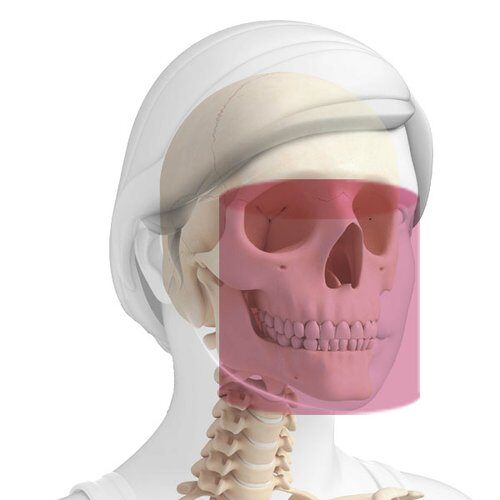

Spécialisations pour lesquelles il est possible d'utiliser le diagnostic 3D.

EXAMENS OTO-RHINO-LARYNGOLOGIQUES

Oreille : 7 x 6 cm (XF)

Nez et sinus maxillaires : 13 x 8 cm

Bouche et gorge : 13 x 10 cm

Ensemble des voies aériennes supérieures : 13 x 16 cm

EXAMENS ODONTOLOGIQUES

AVANCÉS

Dentition jusqu’aux frontaux : 13 x 16 cm

Rami ascendants mandibulaires : 13 x 10 cm

Zygomas et sinus : 13 x 8 cm

Sinus maxillaires : 10 x 10 cm

Éléments dentaires : 4 x 4 cm (XF)

DE BASE

Dentition complète adulte : 10 x 8 cm

Une seule arcade complète adulte : 10 x 6 cm

Dentition complète enfant : 8 x 8 cm

Une seule arcade complète enfant : 8 x 6 cm

Hémi-arcade ou dentition frontale : 6 x 6 cm

EXAMENS ORTHOPÉDIQUES

Articulation Temporo-Mandibulaire : 7 x 6 cm (XF) bouche ouverte/bouche fermée

Rachis cervical : 9 x 9 cm (XF) - Voxel 68 μm

LES VOIES AÉRIENNES

Le FOV 13 x 16 cm permet l’acquisition, en un seul examen, de l’ensemble des voies aériennes supérieures. Visualisation détaillée de la dentition complète, des sinus maxillaires et des voies aériennes supérieures, pour pouvoir identifier clairement tout éventuel rétrécissement et diagnostiquer correctement les syndromes d’apnées obstructives du sommeil (SAOS).